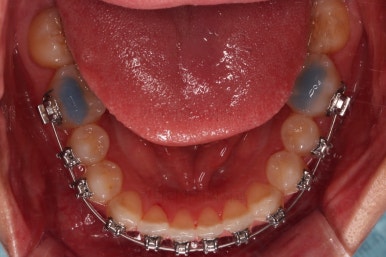

초진 시 입안의 모습이에요.

위아랫니가 모두 삐뚤어요.

특히 앞니가 삐뚤고 위아래 앞니가 고르게 덮여있는게 아니라 뒤죽박죽 엉켜있어서 치아의 마모도 굉장히 많이 되어있는 상태였어요.